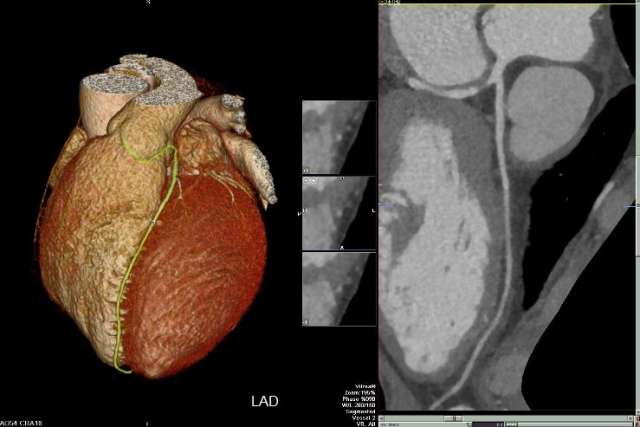

- Coronary Artery Analysis, Calcium Scoring

Coronary Arteries